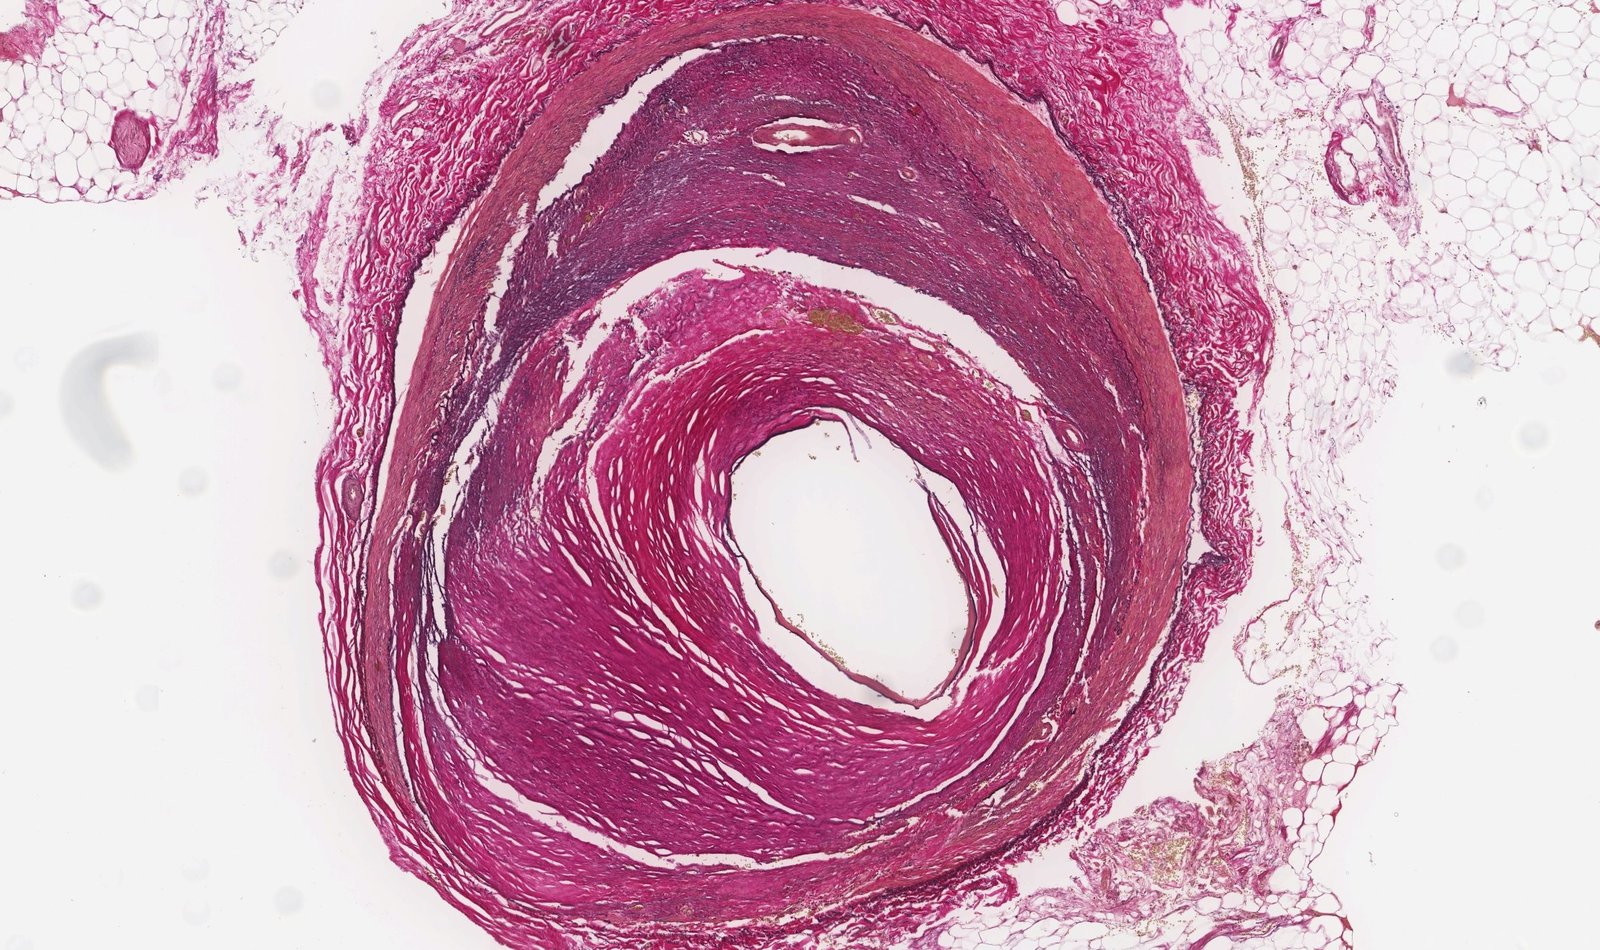

Hyperplastic arteriolosclerosis

- Proliferation of subendothelial smooth muscle cells in response to very high blood pressure

- H&E: "onion-skin" appearance of the arteriole

- Cause: malignant hypertension